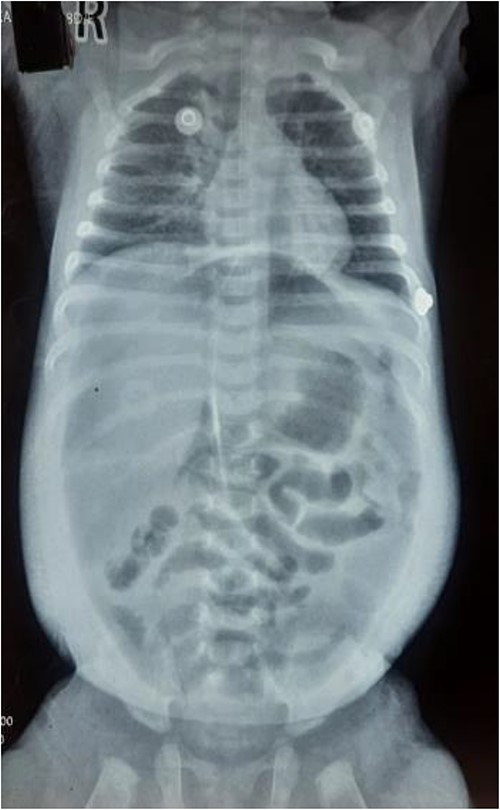

The infant had been previously treated at another facility, where she was admitted in August 2023 due to rhinorrhea, cough, and shortness of breath. She received treatment for Laryngotracheobronchitis (Croup) (Fig. 1) in the pediatric ICU, involving antibiotics, steroids (dexamethasone), nebulization (racemic epinephrine and 3% hypertonic saline), and intravenous fluids. On the sixth day of treatment, she experienced abrupt abdominal distension, leading to nasogastric tube insertion and an immediate referral to our center.

Upon arrival, we conducted a comprehensive medical history review and relevant physical examinations. The baby, delivered via Cesarean section due to fetal distress, had no major health issues except for her mother’s gestational diabetes and a second-trimester urinary tract infection, both managed conservatively. Initial examination indicated signs of dehydration, including a high heart rate, elevated respiratory rate, and 97% oxygen saturation with oxygen support. Abdominal examination revealed distention, visible veins, firmness, and absent bowel sounds. Respiratory and cardiovascular examinations were normal. An erect abdominal X-ray revealed pathological free gas under the right dome of the diaphragm, strongly suggesting a hollow viscus perforation as shown in Fig. 2. Routine blood tests were normal, with a slightly elevated CRP level at 9.5 mg/dl.

Erect X-ray showing pathological free gas under bilateral dome of diaphragm.